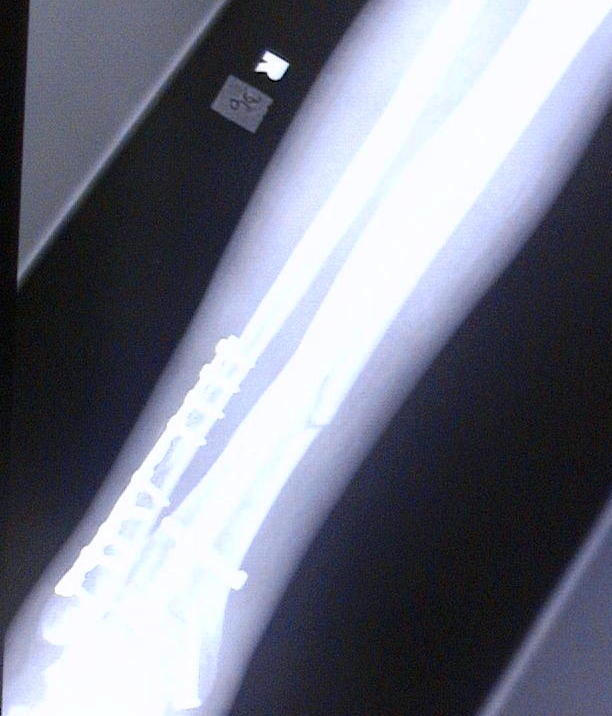

This is Diesel's X-ray's from 9-30-04. He broke hiz tibula on June 21, 2004 doing a 12 o'clock wheelie. Clutch slipped and he flipped over the handle bars and landed ALL hiz weight on hiz right leg causing it to snap.

He just got hiz 3rd cast removed and found out that the bone is not progressing. He now has an walking cast on with a bone stimulator (to maximize circulation to that area) which he will most likely have for the next 6 months. As you can see in the X-Ray's he has a metal plate on the anterior side of hiz ankle where he broke it in 2 places. You can see where the tibula broke and how it is not healing. He has 13 screws and a titanium rod throughout the tibula. Price you pay for being a Stunter!

He just got hiz 3rd cast removed and found out that the bone is not progressing. He now has an walking cast on with a bone stimulator (to maximize circulation to that area) which he will most likely have for the next 6 months. As you can see in the X-Ray's he has a metal plate on the anterior side of hiz ankle where he broke it in 2 places. You can see where the tibula broke and how it is not healing. He has 13 screws and a titanium rod throughout the tibula. Price you pay for being a Stunter! "INSANE STUNTERZ"